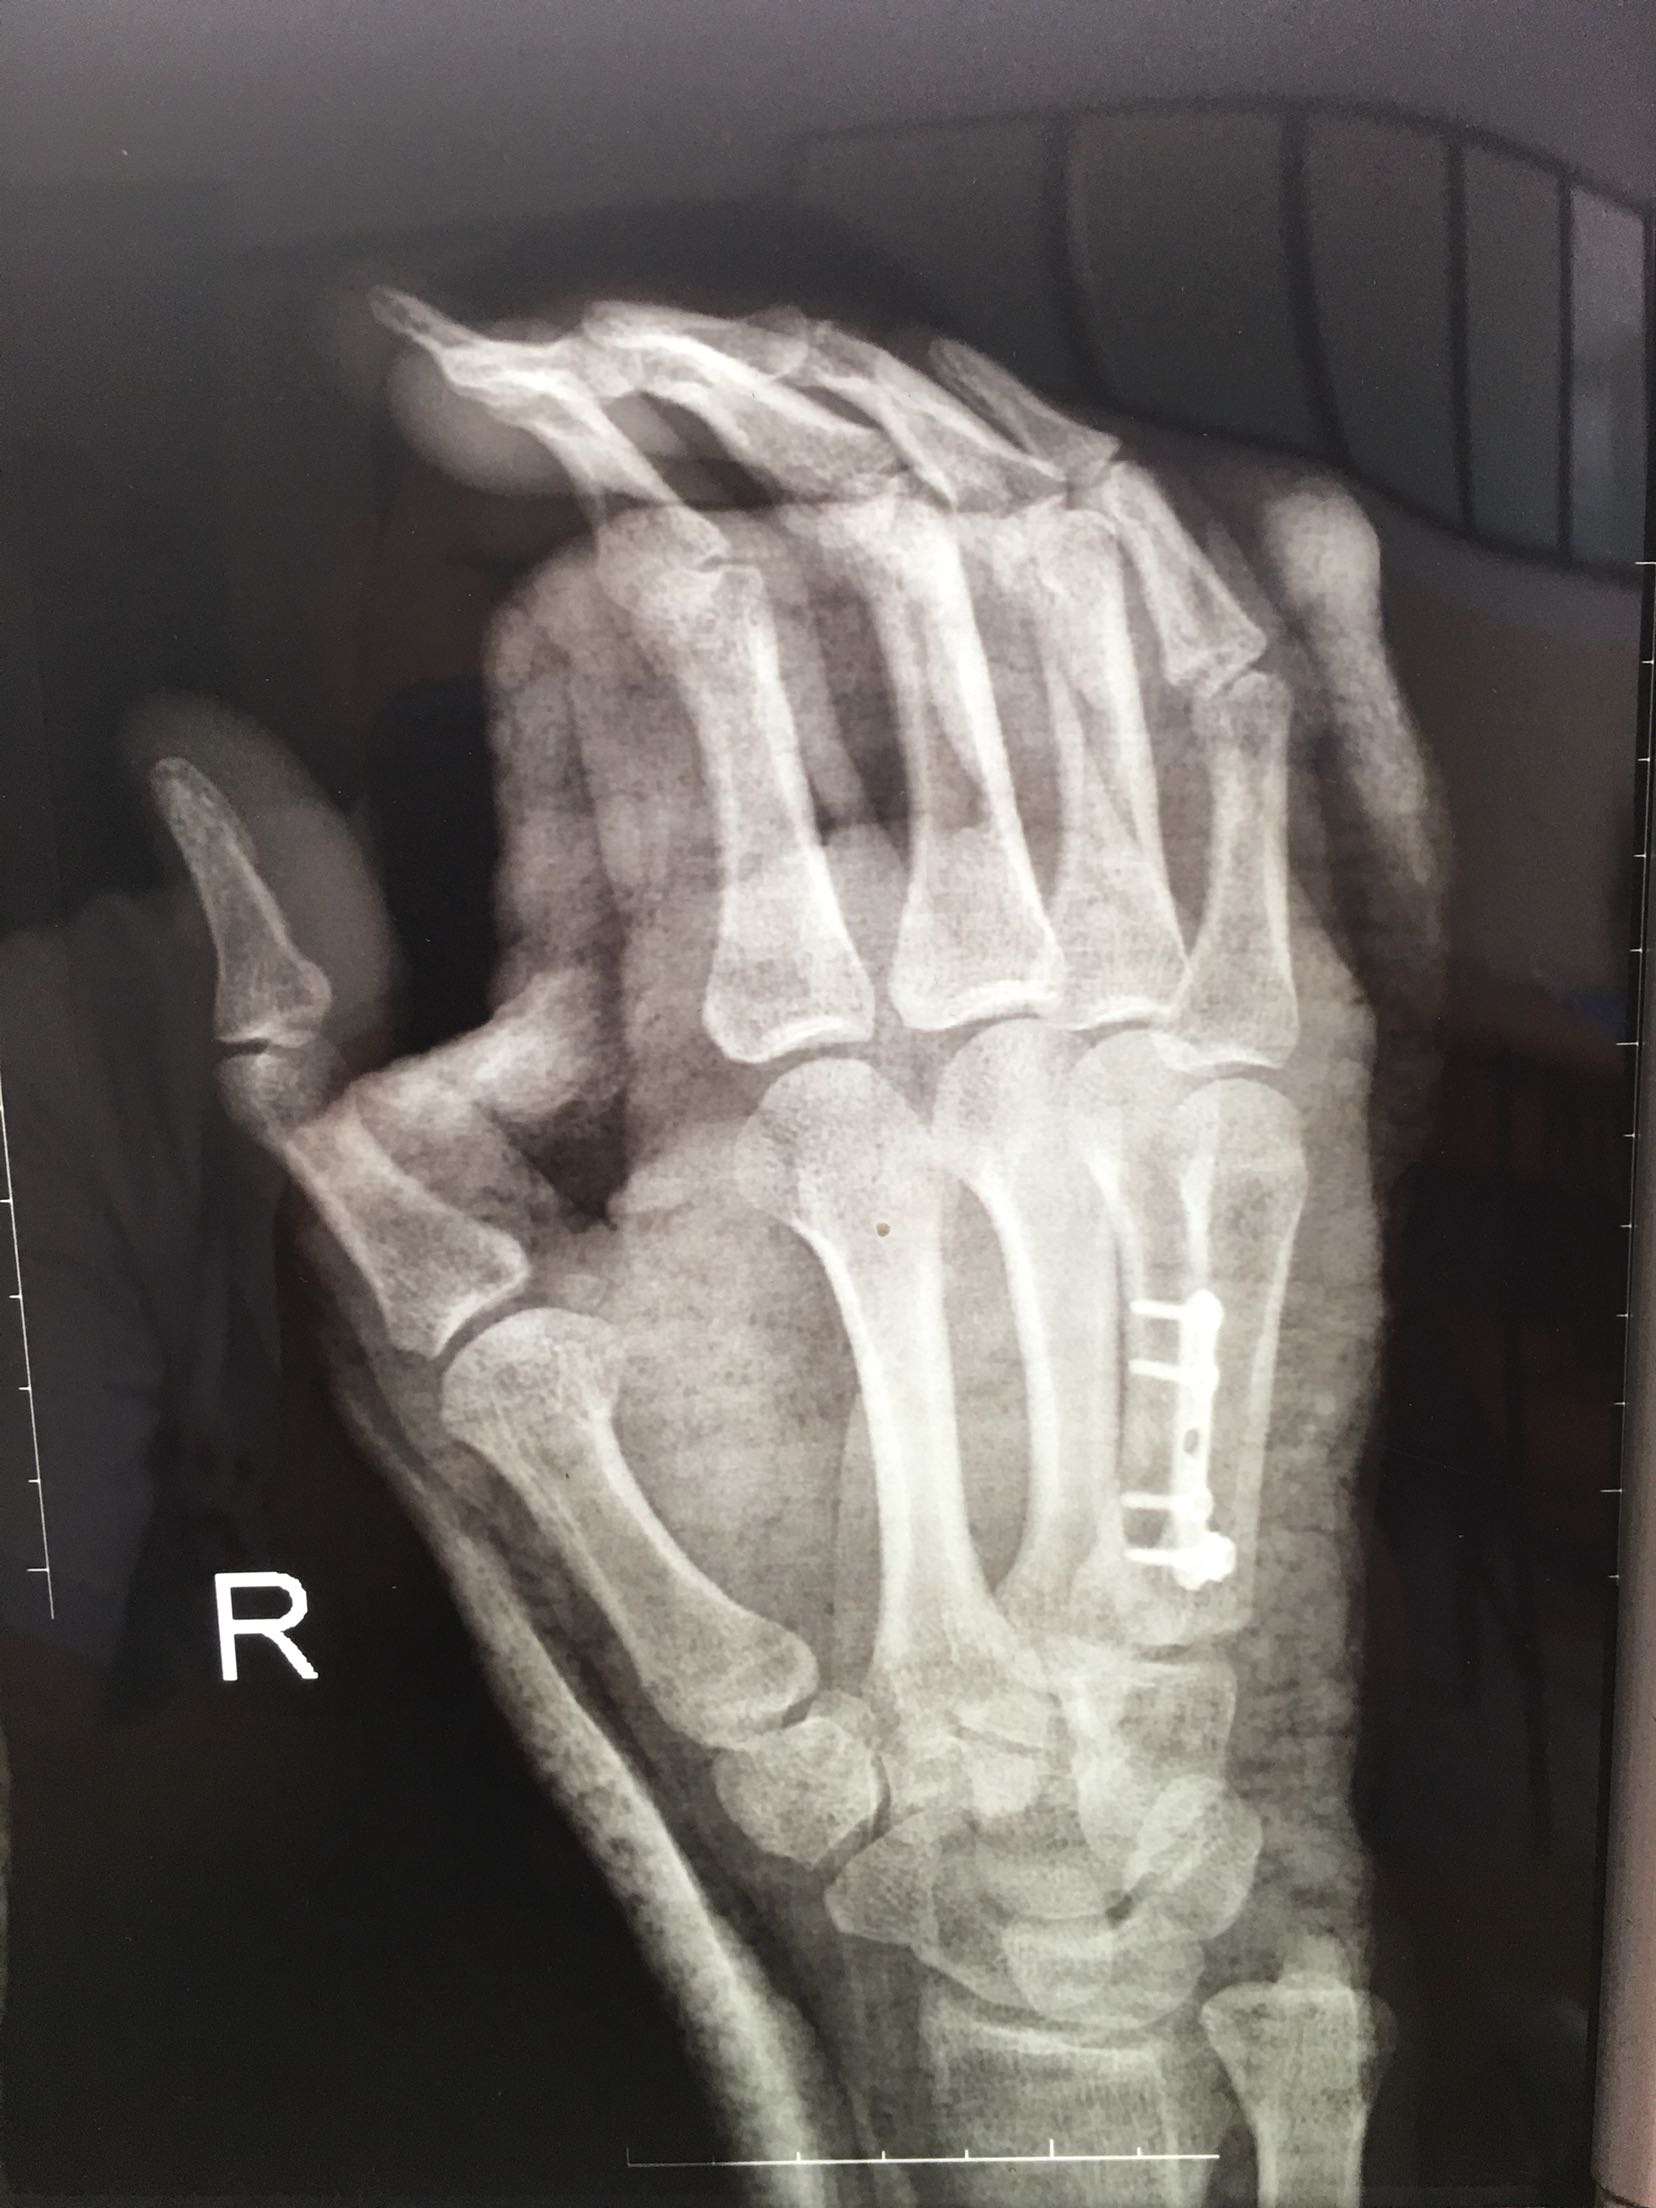

掌骨骨折微钢板固定

患者,男,52岁,摔伤后右手肿痛,活动受限4小时入院。

右手掌肿胀明显,皮色皮温正常,局部压痛,纵叩痛阳性,可及骨擦感,第四掌指关节活动受限,末梢血运感觉正常。

完善检查,在臂丛麻醉下行切复内固定术,术后抗炎,消肿止痛处理。

钢板固定的手术风险?望各位老师指正?谢谢